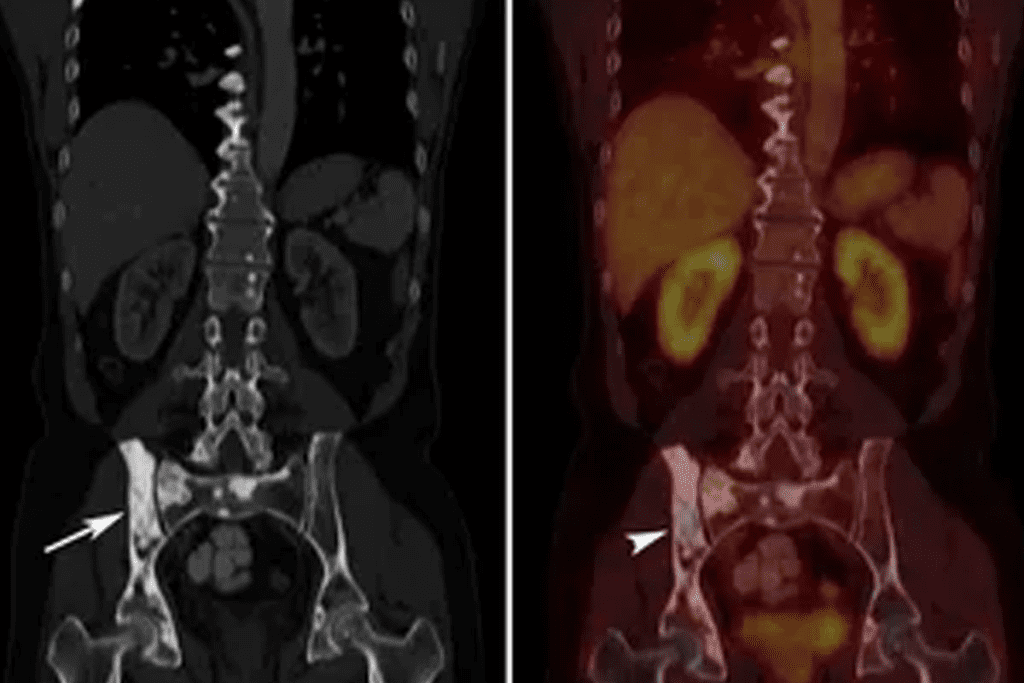

Precise Anatomical Localization of Metabolic Abnormalities

Hybrid PET/CT is excellent at pinpointing where metabolic issues are. This is super useful in tricky areas like the head and neck or pelvis.

As shown in the image below, hybrid PET/CT imaging provides a fused view of PET and CT data, enriching the information doctors have.